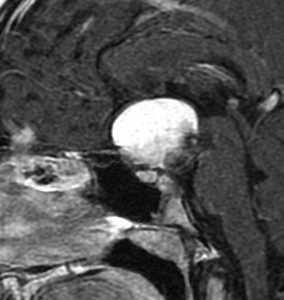

ちょっと大きな頭蓋咽頭腫です

嚢胞(液体が入っている袋)の部分と,腫瘍細胞が固まっている実質部分が入り交じっています。このくらいの大きさになってしまうと,下垂体機能を残すことはとても難しくなります。視神経が圧迫されて視力低下と視野障害を生じます。第3脳室が腫瘍で閉塞していて水頭症になっていますから知能の活動が低下します。

腫瘍を摘出するのに危ないのは,脳の血管の損傷です。左では白く,右では黒く線状に移っているのが太い脳動脈です。これら以外にもたくさんの細い重要な動脈が絡んでいます。

幸いこの患者さんの腫瘍は摘出できて患者さんは元気になりました。でもこのくらいのサイズになると手術がいつもうまくいくとは限りませんし重大な障害が残ることもあります。